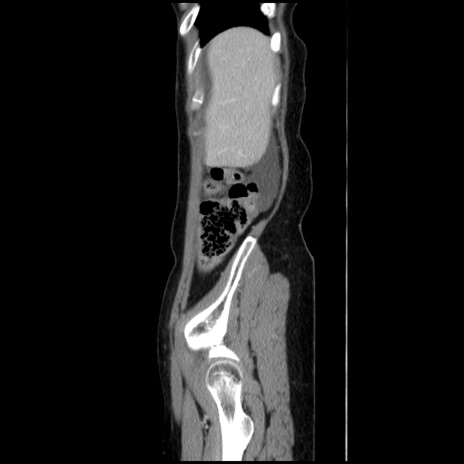

症例32(矢状断像)

【症例】40歳代 女性

【主訴】上腹部痛、嘔気・嘔吐

【現病歴】約9時間前頃から急に上腹部痛、嘔気、嘔吐が出現。改善しないため救急要請。

【既往歴】子宮頚癌(広汎子宮全摘術、放射線療法)、腸閉塞

【身体所見】腹部:平坦、軟、腸雑音亢進、上腹部を中心に腹部全体に圧痛あり。

【データ】WBC 8400、CRP 0.03